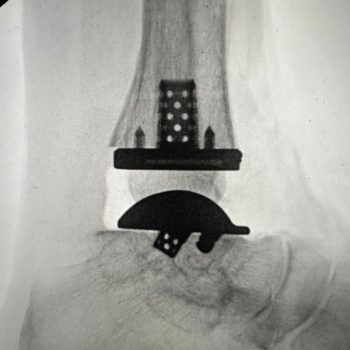

Exactech’s Vantage Ankle 3D and 3D+ tibial implants provide surgeons with tibial stem heights from 10 to 30mm and the added benefits of 3D printing. Additive manufacturing creates a surface that mimics the trabecular nature of cancellous bone. Along with the 3D-printed surface, the implants also feature spiked pegs and a tall sharp central cage, with growing diameters, to aid with initial fixation.

“After several years of developing the 3D+ tibial component with the outstanding Exactech engineers and other design team surgeons, Jim, Jim [Lachman] and I are pleased how the new tibial components and instrumentation seamlessly melded with the existing talar component options. The additive manufacturing, and the press-fit pegs and augmented central cage afford satisfying initial tibial component stability. Particularly exciting is how the intuitive instrumentation allows for reliable and reproducible insertion of a stemmed tibial component through a routine anterior ankle surgical approach.”